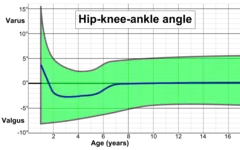

On projectional radiography, the degree of varus or valgus deformity can be quantified by the hip-knee-ankle angle,[7] which is an angle between the femoral mechanical axis and the center of the ankle joint.[8] It is normally between 1.0° and 1.5° of varus in adults.[9] Normal ranges are different in children.[10]

Hip-knee-ankle angle

Hip-knee-ankle angle Hip-knee-ankle angle by age, with 95% prediction interval[10]

Hip-knee-ankle angle by age, with 95% prediction interval[10]